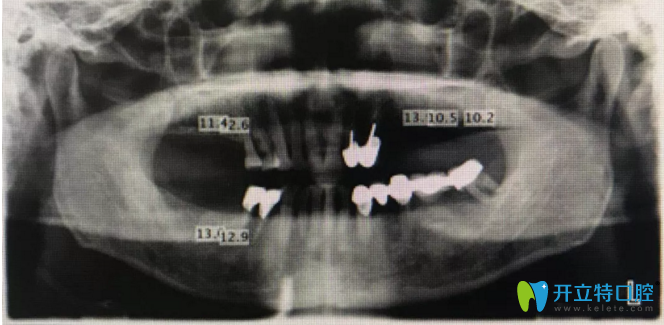

患者資料:17,16,24,25,26,27,47,46缺失3年余,原活動義齒使用不適,咨詢重新制作義齒??趦葯z查缺牙區(qū)牙槽嵴寬度8~10mm,X光檢查,測量骨高度如下所示,非常適合種植修復。

下為術前X光片

術前擬植入位點設計